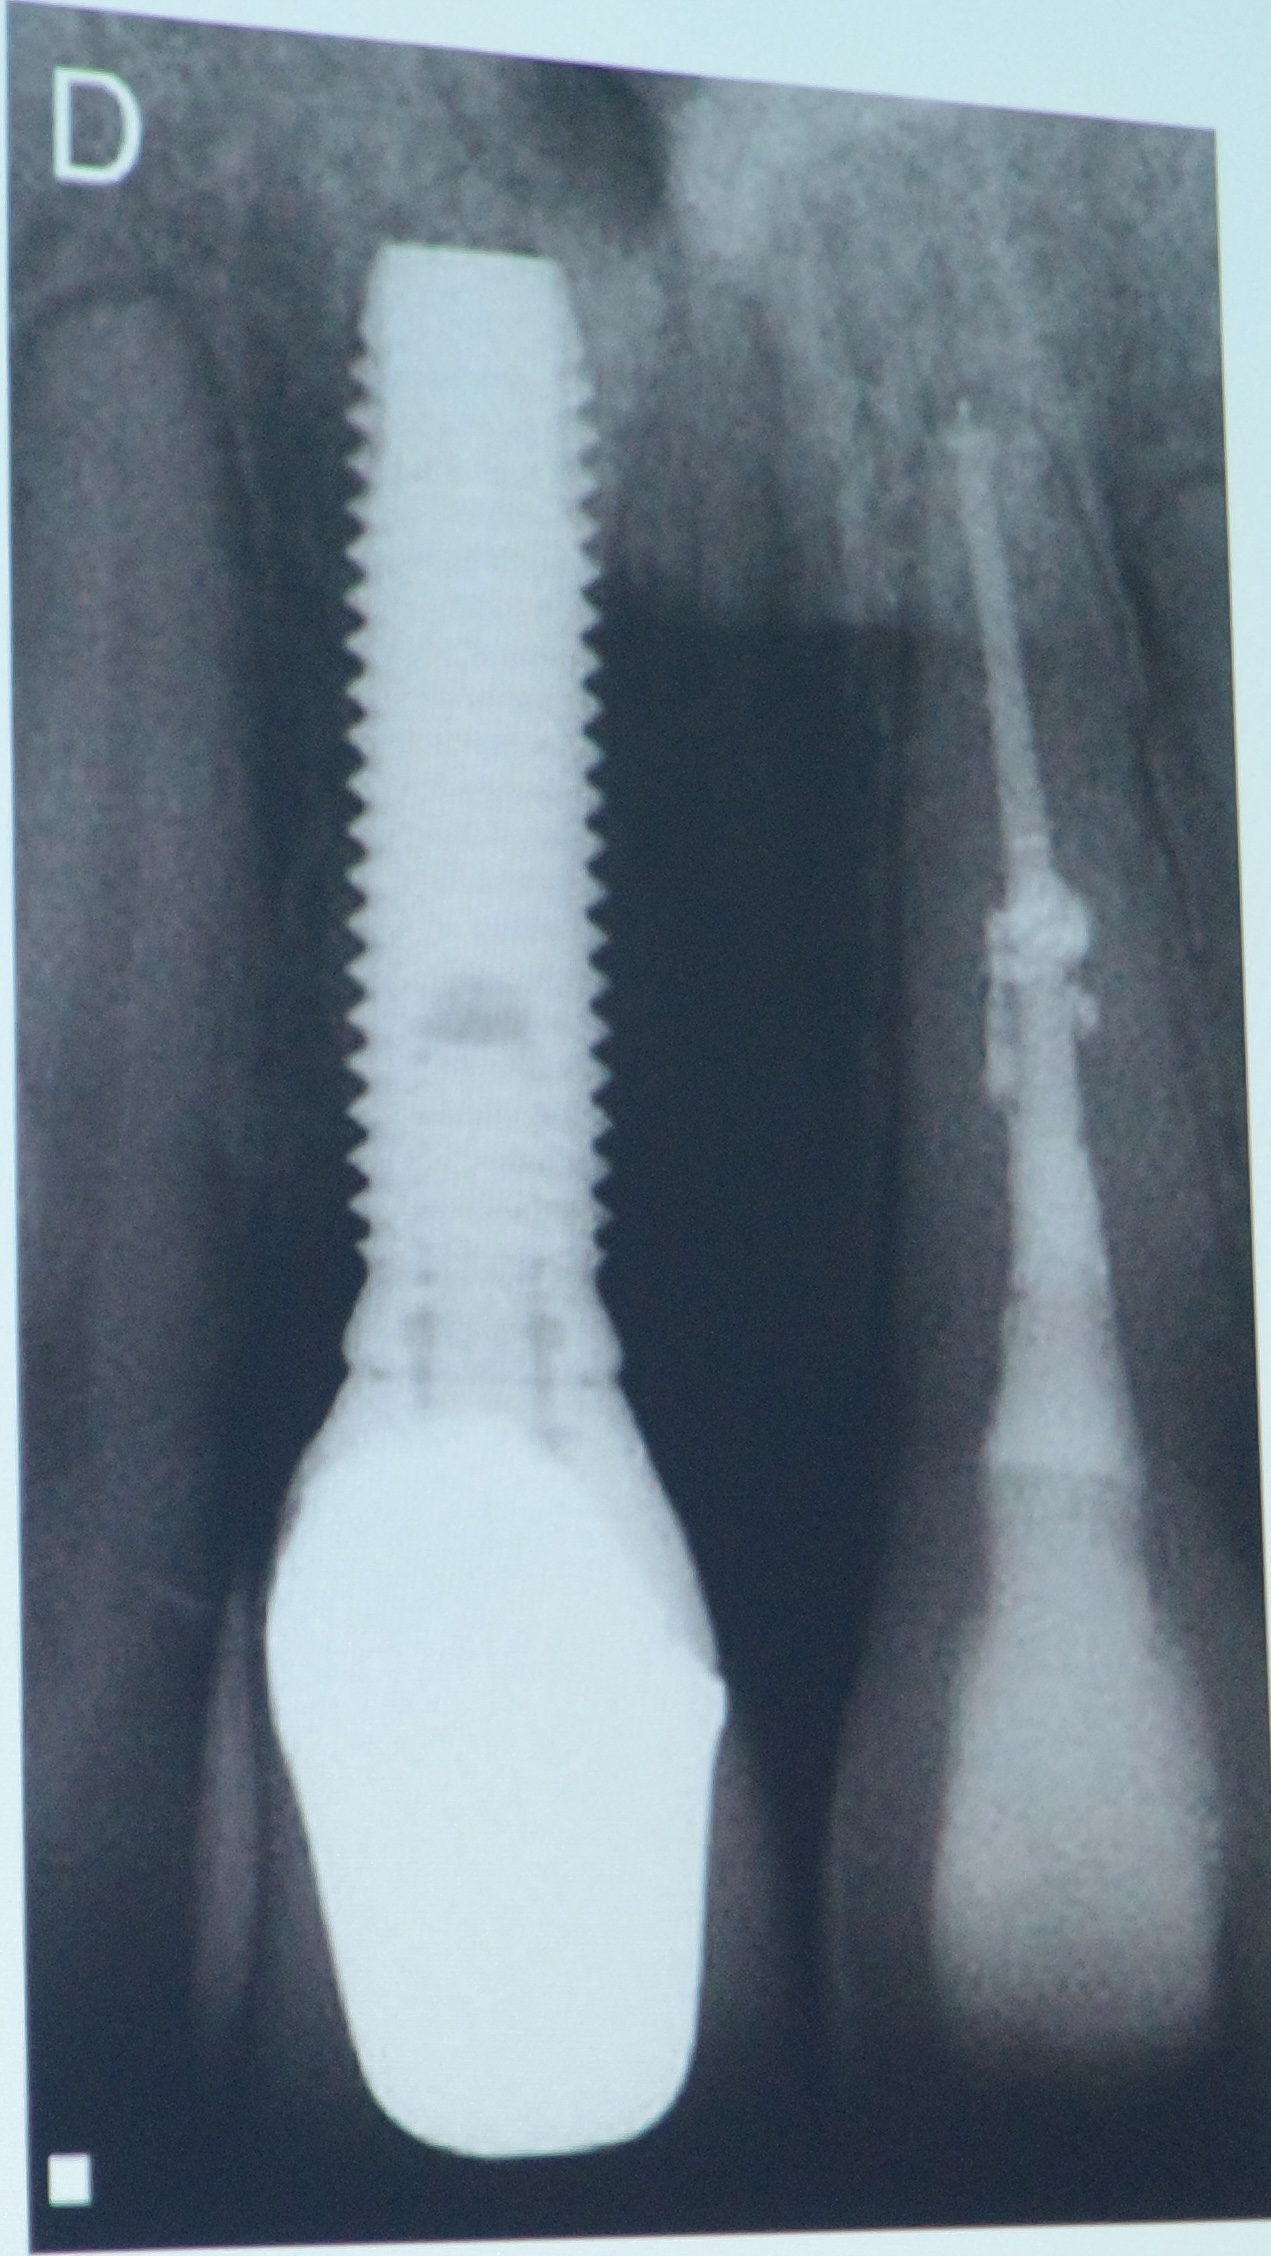

② インプラントとは?

インプラントは、歯を失った部分の顎の骨に人工のチタン製のネジ(フィクスチャー)を埋め込み、その上に人工の歯を装着する治療です。自分の歯のように噛めるのが特徴です。

• 見た目や噛み心地が天然の歯に近い

• 周囲の歯に負担をかけない(ブリッジのように削らない)

• 適切なケアをすれば長期的に安定する

• デメリット

• 外科手術が必要(骨に埋め込む)

• 自費診療のため費用が高い

• 糖尿病や骨粗鬆症など全身の状態によっては適応できない場合がある

• メンテナンスを怠るとインプラント周囲炎(歯周病のような病気)で脱落するリスクがある